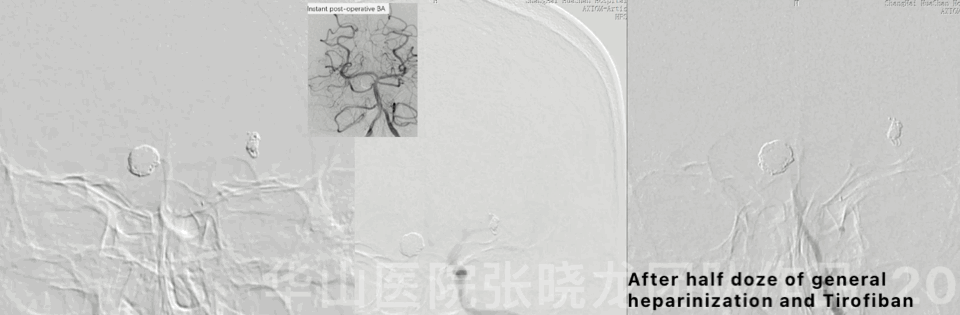

图 20 GIF. 急诊DSA证实右侧小脑上动脉血流缓慢,左侧大脑中动脉通畅。遂经椎动脉予半量全身肝素化和替罗非班5ml,右侧小脑上动脉血流略改善。查体:GCS 15,眼震消失,左侧肌力IV+,双侧巴氏征阳性。替罗非班15ml/h维持。